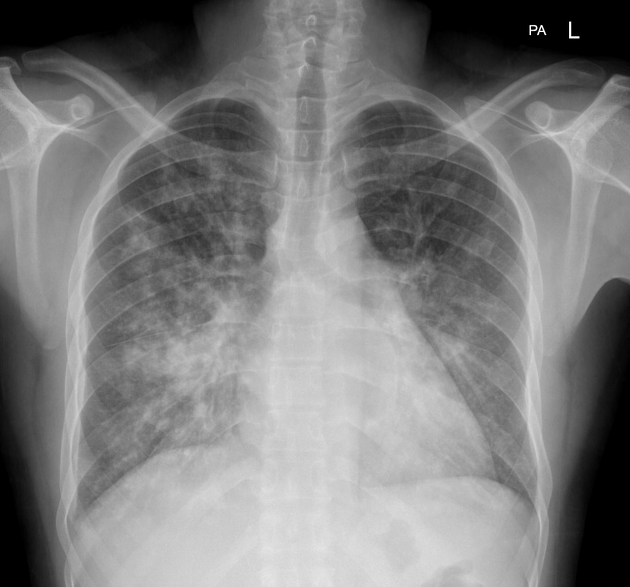

A 21-year-old African American woman presents with difficulty breathing, chest pain, and a non-productive cough. She says she took some ibuprofen earlier but it did not improve her pain. Past medical history is significant for sickle cell disease. Medications include hydroxyurea, iron, vitamin B12, and an oral contraceptive pill. She says she received a blood transfusion 6 months ago to reduce her Hgb S below 30%. Her vital signs include: temperature 38.2°C (100.7°F), blood pressure 112/71 mm Hg, pulse 105/min, oxygen saturation 91% on room air. A chest radiograph is performed and is shown in the exhibit. Which of the following is best initial step in the management of this patient's condition?